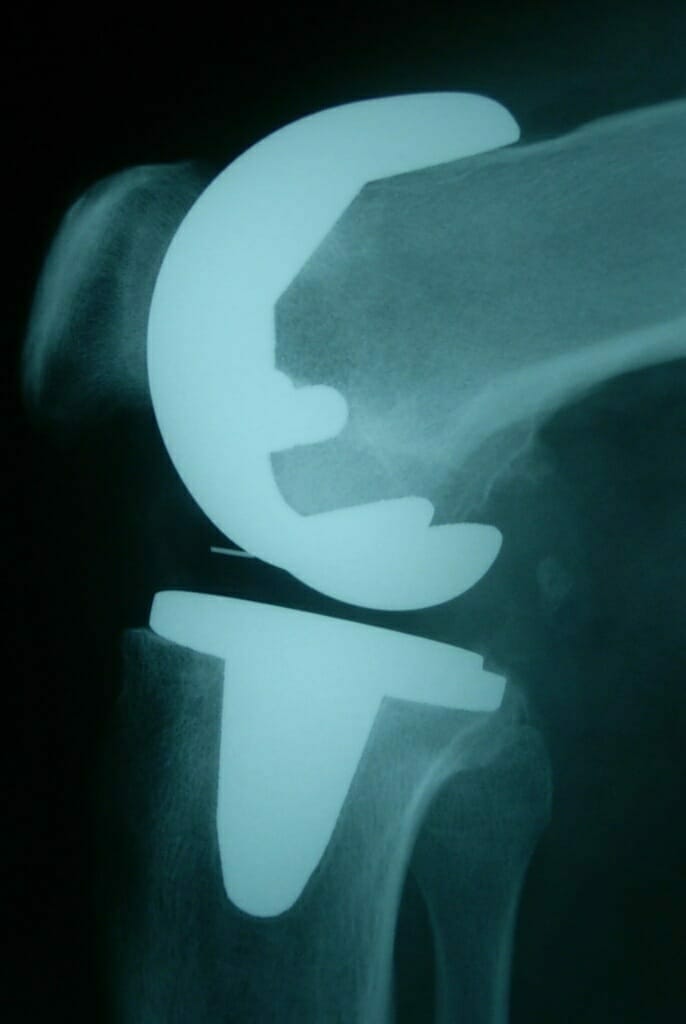

Investigations for arthritis usually entail weight-bearing radiographs of the knee and also a long leg standing alignment x-ray of the leg to show the axes of the leg and knee.